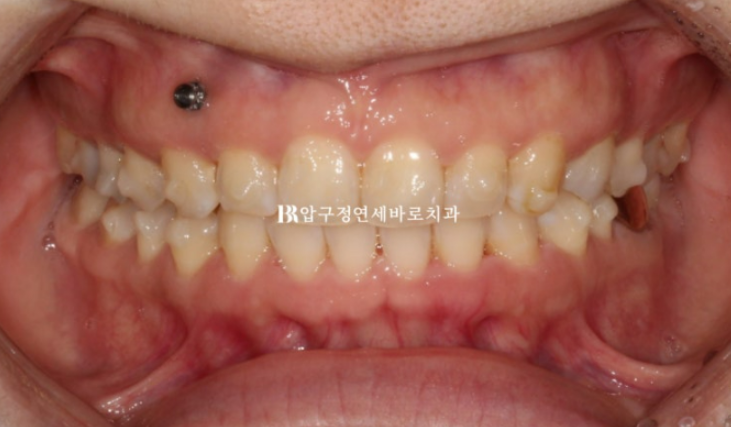

파란 화살표는 임플란트 입니다.

임플란트가 있는 쪽 어금니는 임플란트 치아를 표함하여 이동이 제한이 됩니다.

따라서 임플란트가 있는 쪽 교합을 맞추는 데 한계가 있습니다.

어금니 교합이 좌우 동일하지 않으면 이것이 앞니 중심선까지 영향을 미쳐 중심선이 위 아래가 맞지 않는 상태로 교정이 마무리 됩니다.

이 부분 감수하고 교정치료에 들어갔고 인비절라인 교정을 선택하셨습니다.

켄팅 해결을 위해 한쪽에 미니스크류를 심고 고무줄을 같이 걸어주었습니다.

24년 2월부터 7월까지 5개월간 첫번째 세트의 장치를 다 낀 후 모습입니다.

장치 협조도가 좋아 첫세트에서 과개교합이 완전히 개선이 되었습니다.

뿐만 아니라 앞니 치축 기울어짐, 교합평면 기울어짐도 완전히 해결이 되었습니다.